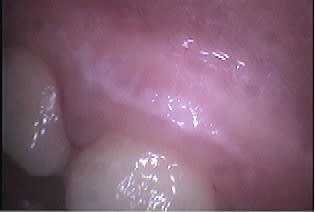

Un autre type d'application en paro du CO² est son utilisation sans photo-ablation en défocalisant à faible puissance, ce qui entraine une cautérisation avec stérilisation, décongestionnement par évaporation de l'inflammation, sédation immédiate des douleurs et biostimulation.

Un exemple la semaine dernière: une patiente de 21 ans reçue en urgence pour un accident d'éruption de la 38 ayant entrainé une névralgie et un trismus avec ouverture limitée à 22mm.

Après utilisation d'un diode HeNe AsGa en mode myorelaxation, ce qui a permis une ouverture en quelques secondes à 30mm, un tir en balayage continu du CO² à 1W a fait disparaitre instantanément la douleur et a porté l'ouverture buccale à 40mm. Le tout a pris seulement quelques minutes.

J'ai alors pu lui prendre une radio et ai poursuivi sans problème par son premier détartrage, la jeune fille étant fumeuse (10 cigarettes par jour depuis 2 ans)... je suis alors tombé sur des leucoplasies au maxillaire que je n'aurai jamais découvertes sans l'aide de mes lasers ou avec une prescription d'AB et AI sans la revoir probablement, ses dents étant impeccables.

Je les lui ai montré et ai essayé de lui faire prendre conscience des risques qu'elle prenait en continuant à fumer sans l'affoler évidemment.